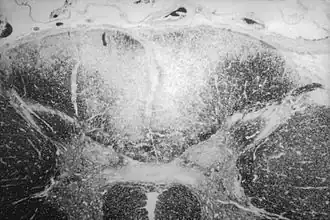

![]() Sección axial de la médula espinal que muestra destrucción sifilítica (área blanqueada, parte central superior) de las columnas posteriores que portan información sensorial del cuerpo al cerebro. | ||

El Tabes dorsal (a veces por su nombre en latín, tabes:íd. Siglo XIX - Consunción, putrefacción y dorsalis de latín dorsum: espalda. Siglo XV - reverso, envés.) es una degeneración lenta de las neuronas sensoriales, que son aquellas que portan la información de los órganos de los sentidos al sistema nervioso central. Los nervios degenerados están en los cordones dorsales (posteriores) de la médula espinal (la porción más próxima a la espalda del cuerpo). Son los nervios que normalmente trasmiten información que ayuda al mantenimiento de la sensación de posición (propiocepción), vibración y tacto discriminativo.

El Tabes dorsal está producido por desmielinización, en la mayor parte de los casos como resultado de una infección por Treponema pallidum, el agente causal de la sífilis.